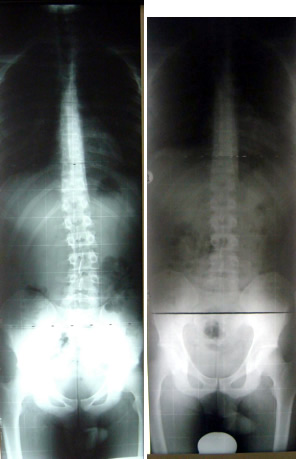

Mädchen, 11 Jahre alt, Skoliose

rechts: nach 24 Monaten